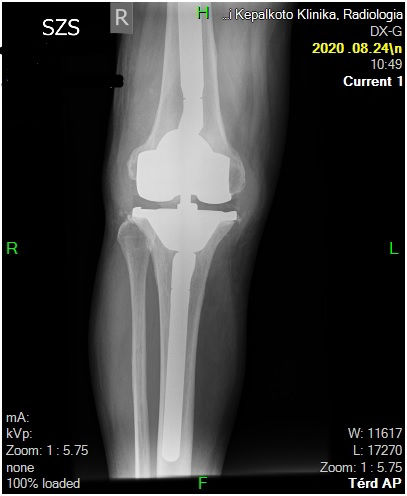

29 éves pályám során közel ezer térdprotézist és több mint kétezer csípőprotézist ültettem be. Az utóbbi években egyre több, nagy műszer igényű, összetett protézis revíziós műtétet végzek.

Fő érdeklődési köröm a biomechanika, műszerfejlesztés, új műtéti technikák kidolgozása és a nagyízületi endoprotetika.